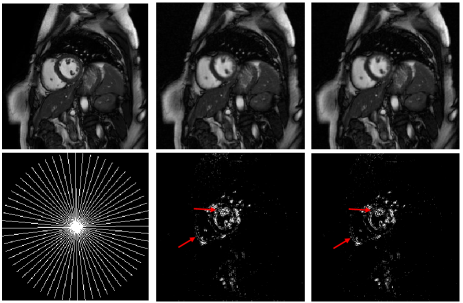

In Fig.1, we compare the recovery results of the TMNN with MNN on a cine cardiac MR image from 30 radial lines (undersampling ratio 0.1) in the noiseless case. We observe that the proposed TMNN model outperforms the MNN method in providing more accurate reconstruction. Fig.2 shows the reconstruction of the cine cardiac MR image from the noisy undersampled measurements using 30 radial lines. In Fig.3, we plot the noisy reconstruction results of the perfusion MR image from the variable density random sampling trajectory with the undersampling ratio of 0.3. It is observed that the TMNN method generates less error compared with the MNN approach. The SNRs of the reconstructed dynamic image using TNN, MNN, and the proposed TMNN at different undersampling conditions are shown in Table.1. We observe that except for one case, the proposed TMNN consistently provides the best reconstruction results and improves the SNR by up to 2dB over the MNN method. In addition, it is shown that the improvement of the proposed TMNN over MNN is more significant in the noisy setting.

Fully sampled MNN recovery TMNN recovery